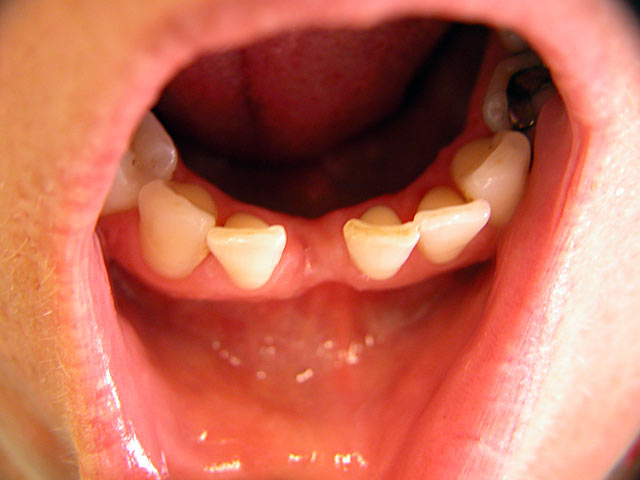

Implantation – Patientenbeispiel 1:

Implantation – Patientenbeispiel 2: